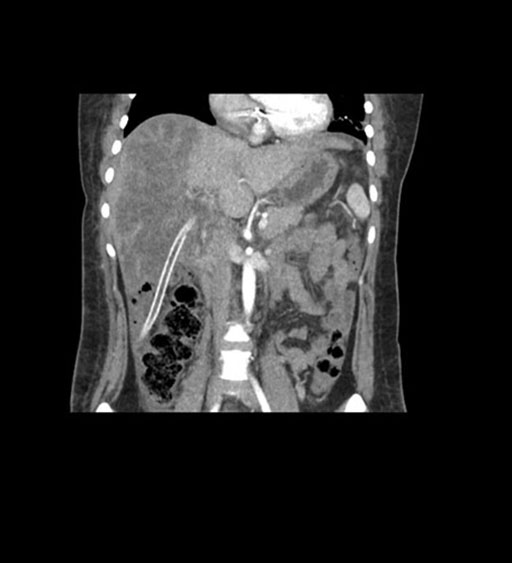

Imaging Analysis

Look through the patient's CT scan to identify any areas of concern for the necessary procedure.

Coronal Arterial

Based on initial findings, which issue(s) would you be most concerned about?